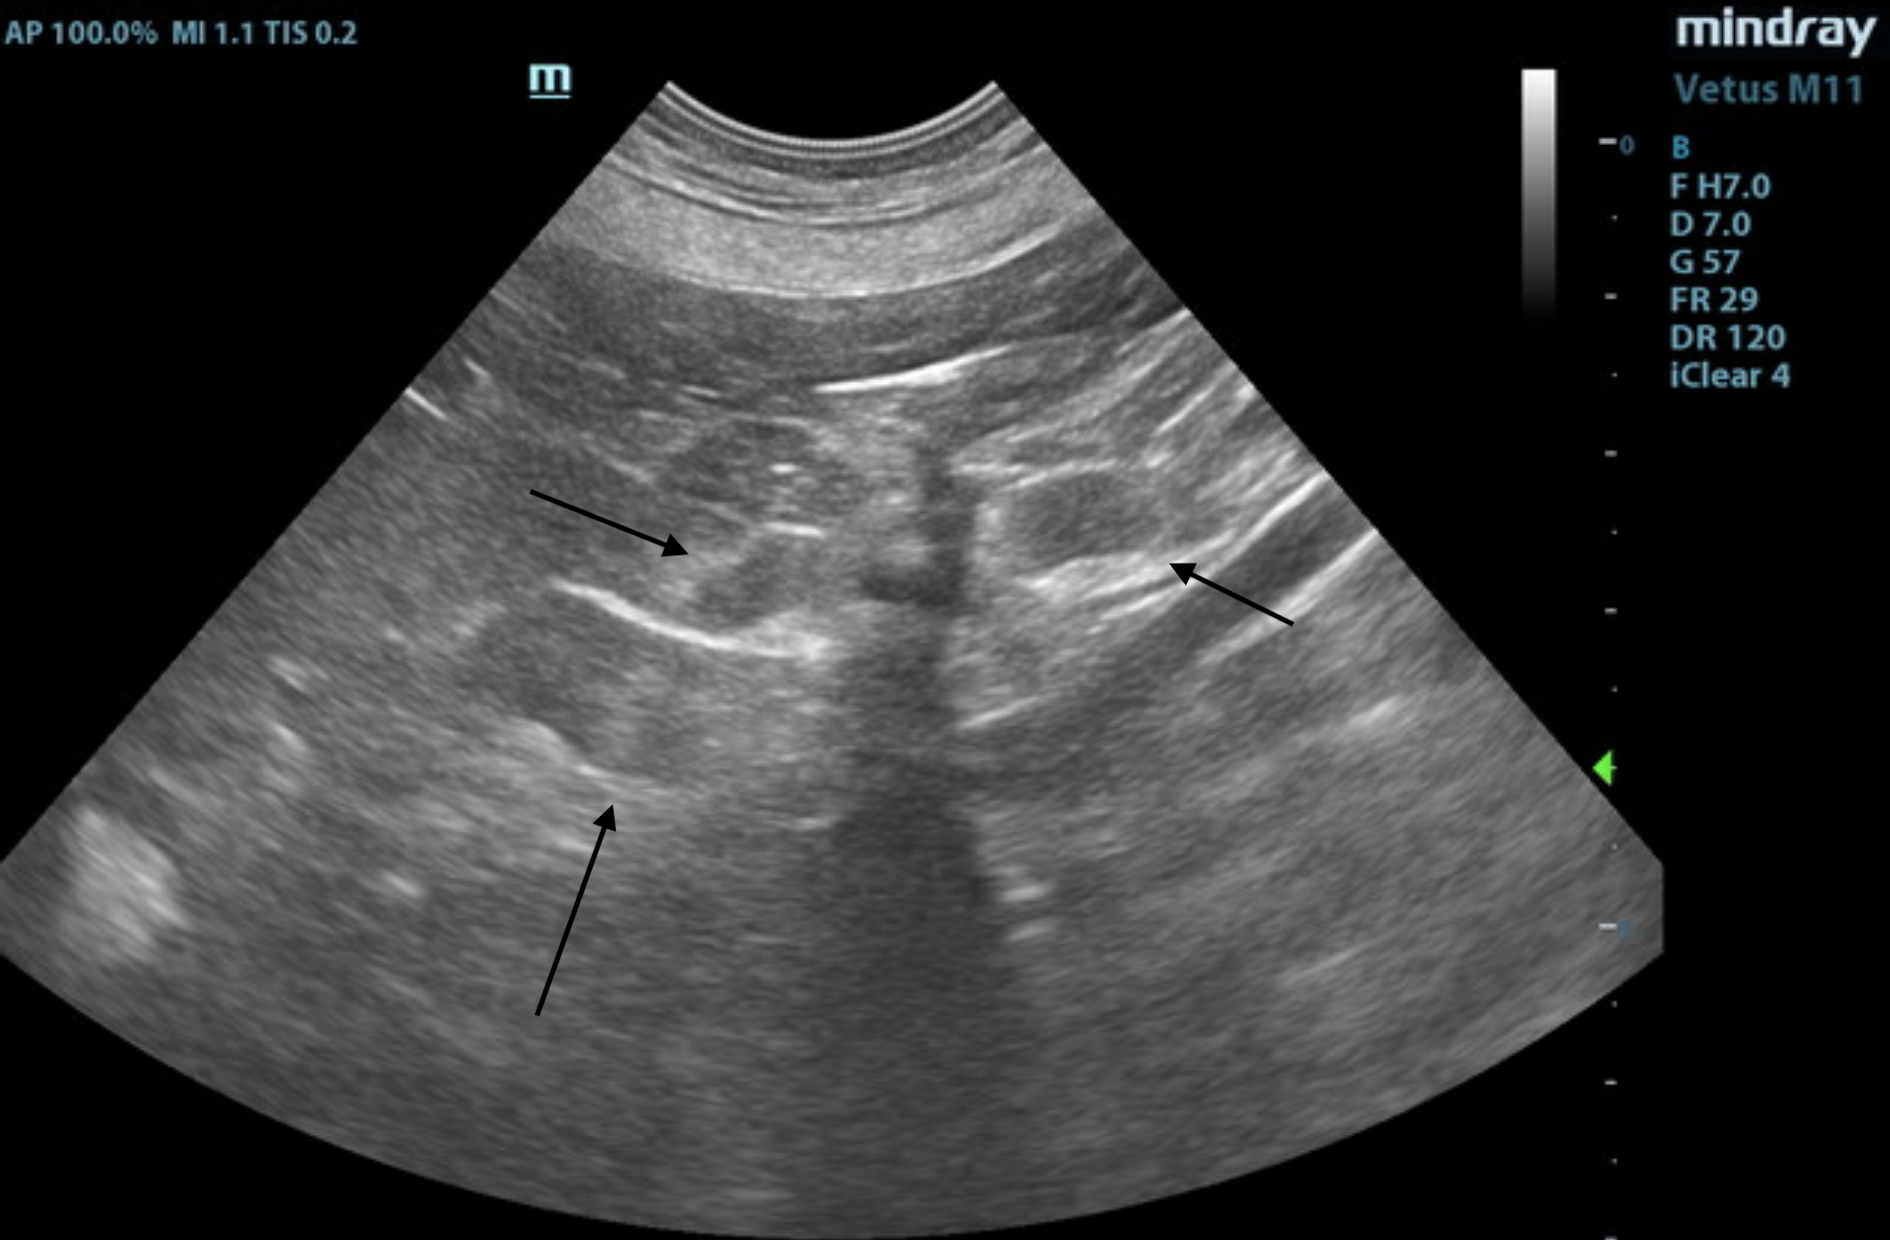

The gastrointestinal presentation revealed mild uniform prominence of the gastric mucosa as well as areas of “ropey” small intestinal wall with slight disruption of the normal 1:3 muscularis/mucosal ratio. The intestinal submucosa was slightly irregular, thickened, and hyperechoic, suggestive of low grade, chronic disease. No evidence of obstruction was present. Chronic inflammatory bowel disease is likely with a low possibility of an early neoplastic event such as lymphoma. Full thickness tissue biopsies via open laparotomy, ideally guided by intraoperative ultrasound in order to obtain the most representative mural sample, would be necessary to rule out this possibility.

Mesenteric lymph nodes were mildly enlarged, reactive.